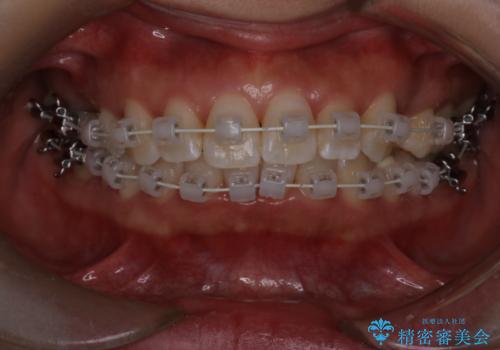

【審美装置】上下の前歯をきれいにしたい

- 矯正装置

- 審美装置

- 治療期間

- 1年8ヶ月

- 上下前歯のがたつきを主訴に来院されました。

口元も下げたいということもあり、上2本抜歯を行い治療を行いました。

抜歯を行い、前歯のがたつき、前歯の出ているところを改善できました。

患者様の満足感も高く治療を終えられました。